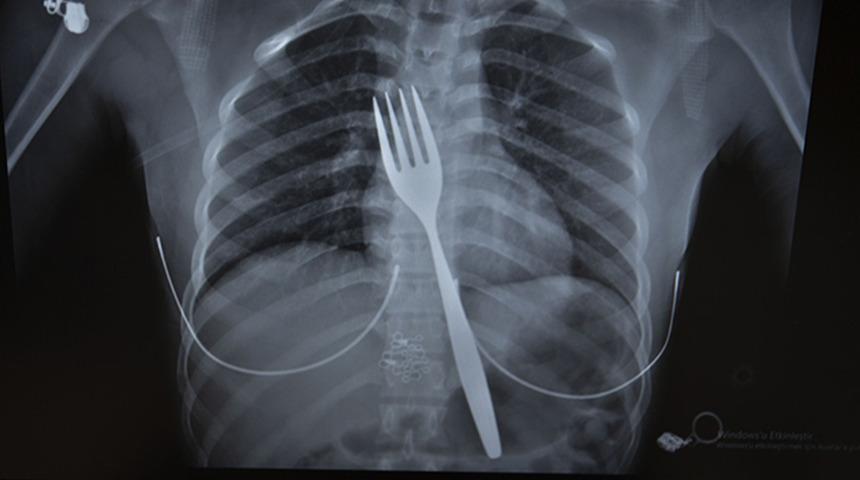

Söke'de yaşayan yabancı uyruklu E.E (18), yemek çatalı yuttuğu şikayetiyle ambulansla Aydın Adnan Menderes Üniversitesi (ADÜ) Hastanesine getirildi. Burada röntgeni çekilen hastanın yemek borusunda 18 santimlik çatal olduğu tespit edildi.

Uzmanlar endoskopi yaparak çatalı ağızdan çıkarmayı denedi. Fakat yemek ve soluk borusuna zarar verme ihtimalinden dolayı midenin kesilerek çatalın çıkarılmasına karar verildi.

ADÜ Tıp Fakültesi Göğüs Cerrahisi Ana Bilim Dalı Öğretim Üyesi Dr. Salih Çokpınar ve Genel Cerrahi Ana Bilim Dalı Dr. Öğretim Üyesi Akay Edizsoy koordinasyonundaki operasyonla midede kesi açılarak çatal çıkarıldı. Bir süre yoğun bakımda kalan hasta, durumunun iyiye gitmesinin ardından servise alındı.

Vakayı ilk duyduğunda şaşırdığını anlatan Edizsoy, "Büyük bir çatalın tamamen yutulması şeklinde ortaya çıkan bu vakayı ilk duyduğumda doğru olmadığını düşündüm. Hasta 18 yaşında ve yabancı uyrukluydu. Türkçesi biraz zayıf olduğu için belki de yanlış anlaşılmalar olabileceğini düşündük. Ama hastanın filmini çektiğimizde gerçekten bir çatalın yemek borusunda olduğunu gördük." dedi.

"Biz en çok bu yüzden tedirgin olduk. Ama ciddi bir yaralanma olmadığını da yapılan endoskopiyle gördük. Endoskopi ile çıkarılamadı çünkü oldukça büyüktü ve endoskopik aletler için uygun değildi. Bu büyük bir yemek çatalı olduğu için kendi ağırlığı da var. Bir çivi gibi, iğne gibi tutulup çekilemiyor. Bundan dolayı karında yapılan kesi ile mideye ulaşıp midenin içinden bunu çıkarmak şeklinde bir strateji izledik. Yaptığımız bu ameliyatla da bu çatalı oradan çıkarabildik."